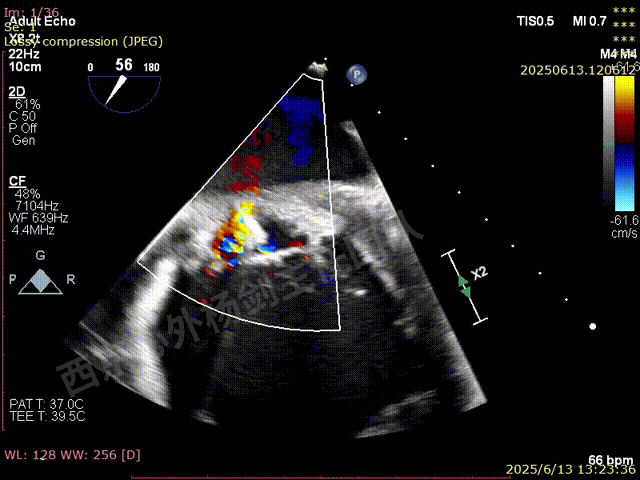

TAVR术后,全心增大,二尖瓣反流重度,三尖瓣反流重度。中量心包积液。左室严重增大,标准图像调整困难。主动脉瓣位带支架人工瓣膜瓣叶启闭正常,主动脉瓣位人工瓣上血流速度Vmax 148cm/s,PGmax 9mmHg,Vmean 86cm/s,PGmean 2mmHg, VTI 34.7cm,瓣周反流(轻)。估测肺动脉收缩压约49mmHg;左室收缩功能明显减低。LVEF:23%,EDV:364ml,ESV:221ml。

彩色血流示:二尖瓣反流缩流颈彩宽6.6mm,面积17cm²,容积30ml;二尖瓣瓣口面积6.6cm²,瓣环内径:左右径34mm,前后径34mm。2区瓣叶长度:前叶36mm,后叶20mm,叶环比1.6. 三尖反流面积17.2cm²,容积33ml,Vmax 291cm/s,PGmax 34mmHg。

TEER术前超声评估

二尖瓣后叶栓系严重,前叶相对错位,反流束沿2区分布广泛,2偏3区处存在反流。

反流宽度至少23mm,因影像调整困难,考虑实际反流更宽。